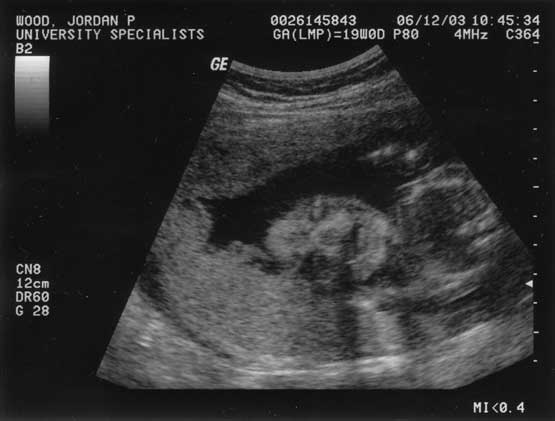

Baby's First Ultrasound

Today we got to see the baby. Click for a closer view. The third picture shows the foot measurement-- about an inch. The rest are images of the baby's face, if you can call a cross-section of bone and soft tissue a face.

June 12, 2003